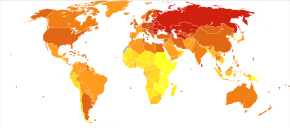

In 2013 CAD was the most common cause of death globally, resulting in 8.14 million deaths (16.8%) up from 5.74 million deaths (12%) in 1990.[6] The risk of death from CAD for a given age has decreased between 1980 and 2010 especially in developed countries.[19] The number of cases of CAD for a given age has also decreased between 1990 and 2010.[20] In the United States in 2010 about 20% of those over 65 had CAD, while it was present in 7% of those 45 to 64, and 1.3% of those 18 to 45.[21] Rates are higher among men than women of a given age.[21]

CAD as of 2010 was the leading cause of death globally resulting in over 7 million deaths.[87] This is up from 5.2 million deaths in 1990.[87] It may affect individuals at any age but becomes dramatically more common at progressively older ages, with approximately a tripling with each decade of life.[88] Males are affected more often than females.[88]

It is estimated that 60% of the world's cardiovascular disease burden will occur in the South Asian subcontinent despite only accounting for 20% of the world's population. This may be secondary to a combination of genetic predisposition and environmental factors. Organizations such as the Indian Heart Association are working with the World Heart Federation to raise awareness about this issue.[89]

Coronary heart disease (CHD) is the leading cause of death for both men and women and accounts for approximately 600,000 deaths in the United States every year.[90] According to present trends in the United States, half of healthy 40-year-old men will develop CAD in the future, and one in three healthy 40-year-old women.[91] It is the most common reason for death of men and women over 20 years of age in the United States.[92]